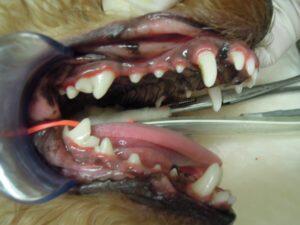

1.右側外観です。

3.まず、スケーリングをして口の中をきれいにしてから

4.プロービング検査で歯周ポケットの深さを測定して